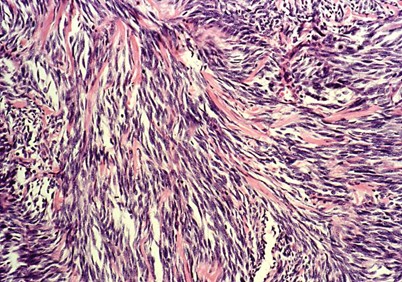

Weichgewebssarkome

Sarkome sind seltene Tumoren, die entweder in den Knochen oder in den Weichgeweben auftreten. Dazu gehören das Muskel-, Fett-, Knorpel- und Bindegewebe, aber auch Gefäße. Sarkome umfassen bis zu 100 verschiedene, bösartige (= maligne) Tumoren. Diese unterscheiden sich teilweise deutlich in ihrem biologischen Verhalten, ihrer Prognose und ihrem Ansprechen auf unterschiedliche Therapien.